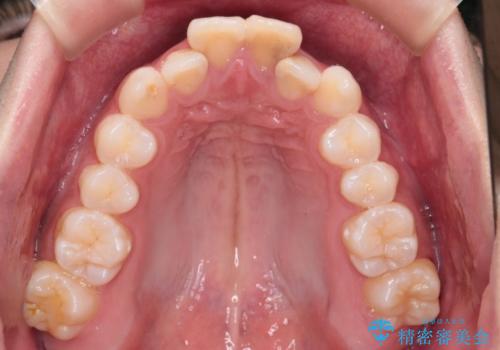

- 前歯が出ていることを主訴に来院されました。

臼歯関係が上顎前突傾向のため、上顎小臼歯を抜歯してインビザラインにて治療を行いました。